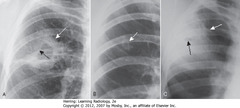

Cervical Intraepithelial Neoplasia (CIN)

Dysplastic growth at the cervical transformation zone caused by high-risk HPV that destroy tumors suppressors (p53/Rb) Characteristics: - koilocytic change - nuclear atypia - increased mitosis Grading (higher grade is less likely to reverse): - CIN 1 (mild - 1/3 of epithelium) - CIN 2 (moderate - 2/3 of epithelium) - CIN 3 (severe - most of epithelium) *all of the above are REVERSIBLE - Carcinoma in situ (all of epithelium) *NON-REVERSIBLE